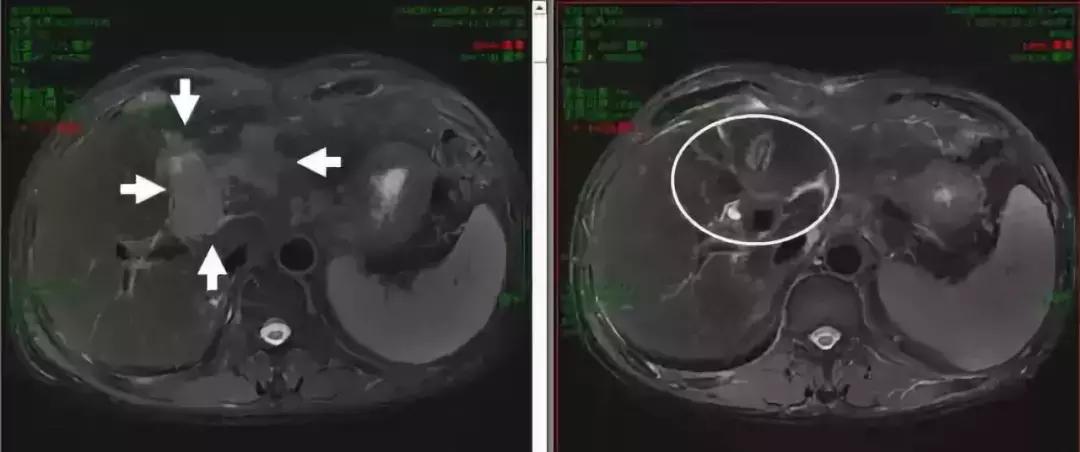

肝动脉栓塞治疗是不可手术中晚期肝癌的重要治疗手段,据报道TACE治疗疗效优于支持治疗,6个月客观有效率约35%-39%。但是,由于肝细胞肝癌具有肝动脉和门静脉的双重血供的特点,仅仅动脉栓塞化疗难以完全根治肝细胞肝癌,2年生存率约31-63%。北京大学肿瘤医院王维虎教授团队研究显示,TACE术后联合放疗,客观有效率高达80%(如图2)。2015年,一项关于TACE联合放疗对比单纯TACE的系统回顾性荟萃分析纳入了25个临床研究,共包括2577例肝癌患者。研究显示,在肿瘤治疗有效率和1、2、3、4、5年生存率方面,TACE+放疗较单纯TACE有明显优势。不可手术的晚期肝癌总体治疗疗效不佳,对局限于肝内的肝癌,接受介入栓塞化疗后仍有肿瘤残存,放疗可以提高疗效,进一步延长患者生存期。

图2 放疗联合TACE治疗后核磁共振显示:肝癌明显缩小,放疗前肿瘤大小9.7cm(左图),放疗后1月

原发性肝癌在就诊时,瘤栓发生率高达10%~40%,这部分患者缺乏有效的治疗手段,对症支持治疗后中位生存只有2-4月,但近年研究显示,放疗对瘤栓的有效率>50%。通过包括放疗与TACE等在内的综合治疗后,中位生存时间可达到12月左右(如图3)。即便是有骨转移、肾上腺转移患者,行放疗后疼痛缓解率也高达80%。

图3 核磁共振显示:放疗前门脉左支瘤栓3.8x6.6cm(左图),放疗后2月瘤栓消失(右图)。